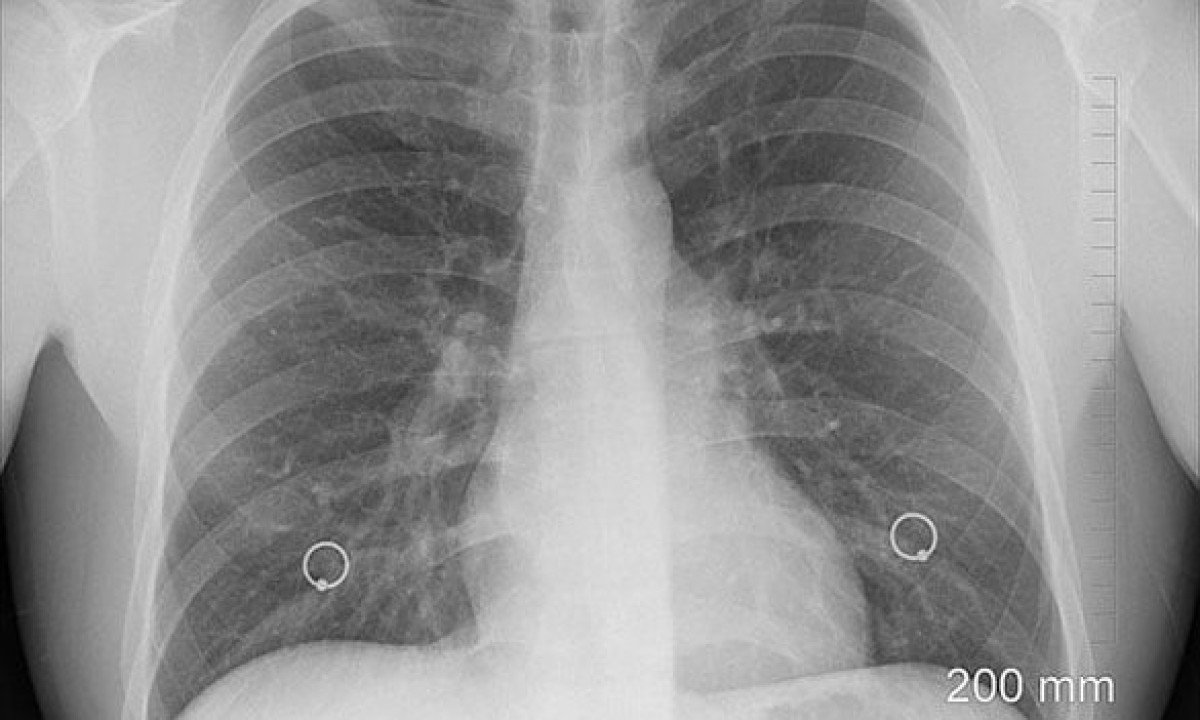

Por isso, no caso de qualquer preocupação com seus pulmões, Dickinson recomenda consultar um médico em busca de um teste de função pulmonar apropriado. Ele envolve respirar em um aparelho chamado espirômetro, que mede o volume e a velocidade da respiração.

O espirômetro irá calcular sua CVF com precisão de grau médico, além do seu volume de expiração forçada (VEF1), que é a quantidade de ar que você consegue exalar em um segundo, após uma respiração profunda.

O aparelho também fornecerá a razão entre o VEF1 e a CVF, o que pode indicar eventuais obstruções do fluxo respiratório. Combinadas, estas medidas fornecem um quadro geral da saúde pulmonar.